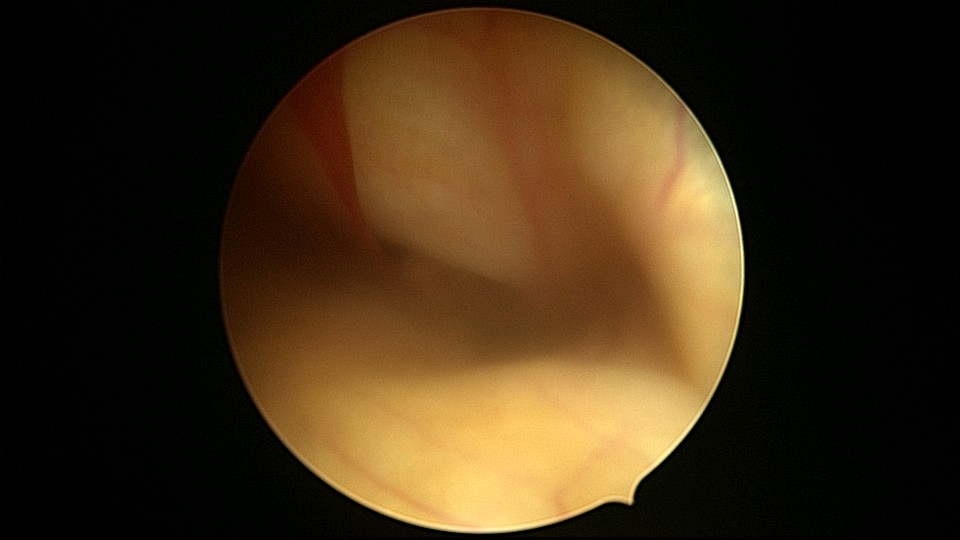

患者48岁,G3P1,顺产1次。安环10年,绝经1年,外院取环失败,子宫穿孔,腹部平片无异常。宫腔镜见宫腔广泛致密粘连,V型环与粘连组织嵌顿,取环钩盲视下多次尝试钩取节育环,均失败。取环钩循镜鞘外侧进入宫腔,直视下钩住节育环,顺利取出。再次置镜寻找子宫穿孔处并进入盆腔,见网膜脂肪组织,确认无活动性出血及盆腔积血,结束手术。